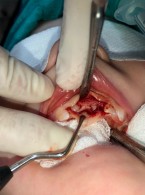

Chirurgiczne leczenie intruzji zębów mlecznych. Opis przypadku

Zobacz więcej

12.50PLN